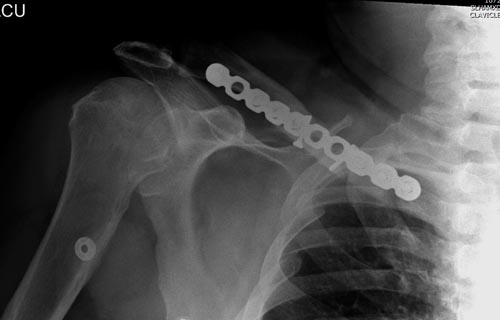

Болезненные ложные суставы надо оперировать, и здесь представлен случай

свежего болезненного ложного сустава, оперированного через 4 месяца.

Освобожден средний фрагмент и боковая компрессия лагированием, фиксация

пластиной..